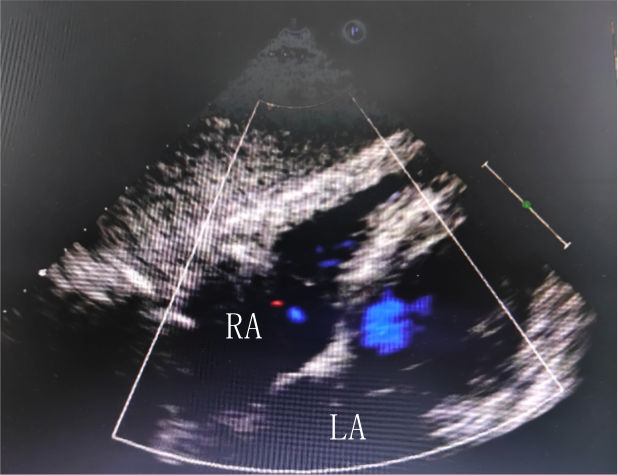

左图:经胸超声未发现卵圆孔未闭

右图:经食管超声发现宽约1.2mm的PFO